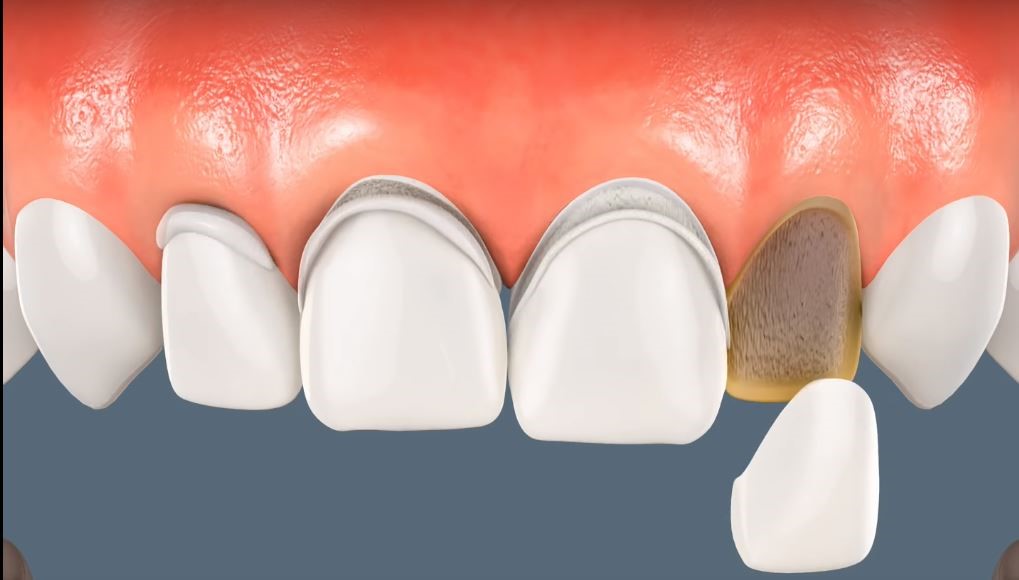

فينير الأسنان، أو ما يُعرف أيضاً بالعدسات اللاصقة للأسنان، هو عبارة عن قشور رقيقة جداً (بسمك 0.3 إلى 0.7 ملم) تُصنع من مواد خزفية عالية الجودة أو مواد مركبة، وتُلصق على السطح الأمامي للأسنان لتحسين مظهرها.

تخيل الفينير كأنه “قناع تجميلي” رقيق جداً يغطي واجهة السن، يمنحك ابتسامة ناصعة البياض ومتناسقة تماماً. هذه القشور مصممة خصيصاً لكل مريض بحيث تتناسب مع شكل وجهه ولون بشرته، مما يضمن نتيجة طبيعية وجذابة.

الجلسة الثانية: التحضير

نقوم ببرد طبقة رقيقة جداً من سطح السن الأمامي (حوالي 0.5 ملم) لإفساح المجال للفينير. هذا الإجراء غير مؤلم ويتم عادةً تحت التخدير الموضعي لضمان راحتك التامة. بعد ذلك، نأخذ طبعة دقيقة جداً لأسنانك ونرسلها إلى المختبر المتخصص. في هذه الأثناء، نضع فينير مؤقت لحماية أسنانك المحضّرة.

الجلسة الثالثة: التركيب النهائي

عندما يصل الفينير الدائم من المختبر (عادةً بعد أسبوع إلى أسبوعين)، نزيل الفينير المؤقت ونجرب الفينير الدائم للتأكد من ملاءمته ولونه. بعد موافقتك، ننظف الأسنان بعناية ونستخدم مواد لاصقة خاصة لتثبيت الفينير بشكل دائم. أخيراً، نزيل أي فائض ونلمع الفينير لإعطائه اللمعان الطبيعي.